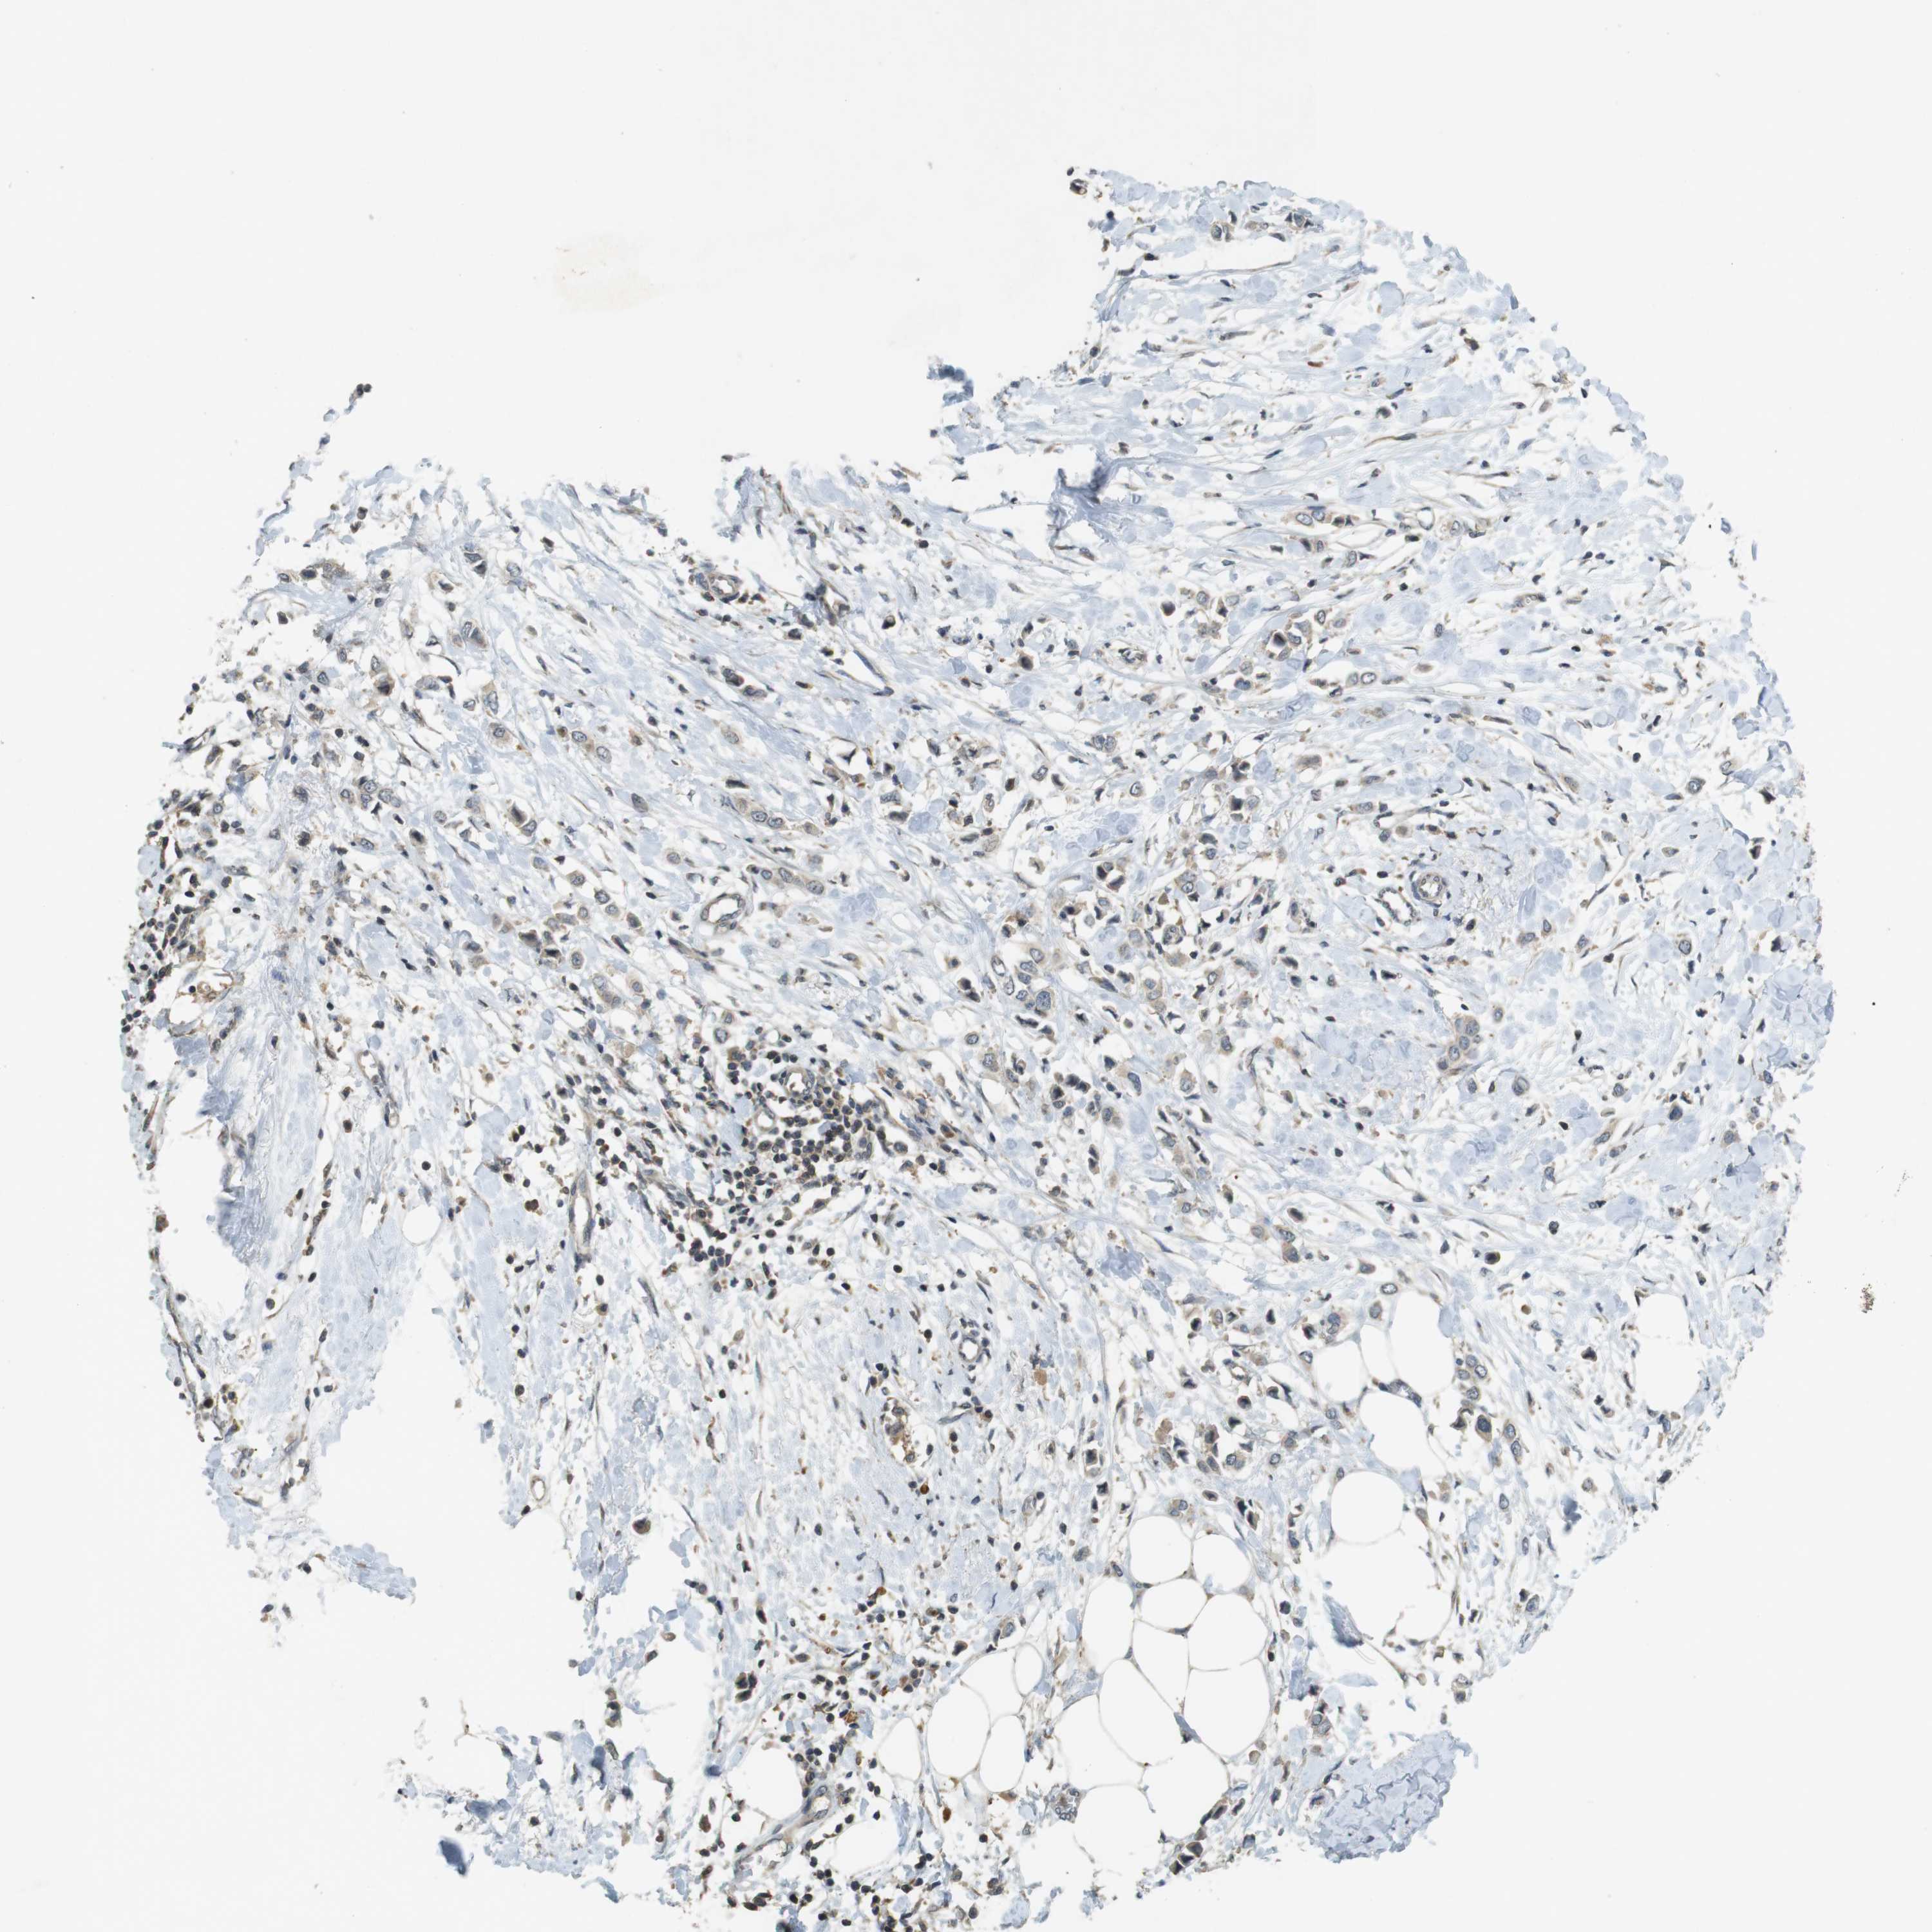

CANCER BREAST CANCER Show tissue menu

BRCA TCGA BRCA VALIDATION PROTEIN EXPRESSION

ANTIBODIES

AND

VALIDATION